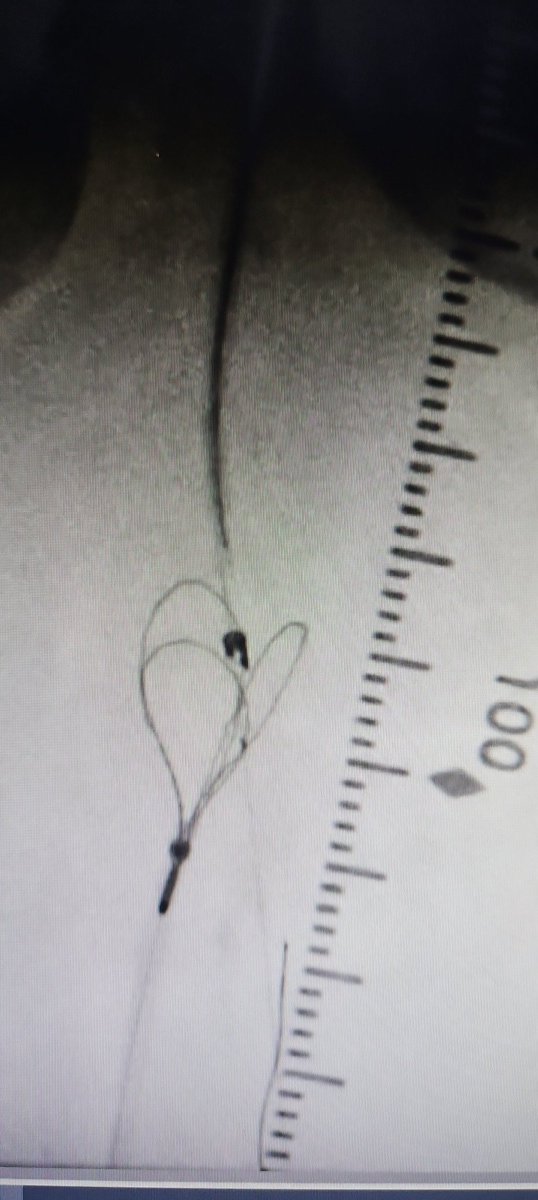

First glimpse of #PTAB w #Detour @endologix 3 week surveillance arterial duplex @ShawnPenn33 @DeanFerreraDO @MarcoShaker @kymbee @tlevin

We completed the first 2 perc bypass in Illinois w #Detour @endologix Excited for this groundbreaking technology to be in the hands of #limbsalvage docs around the globe. @ShawnPenn33 @DeanFerreraDO @Abd_Alrifai @MarcoShaker @tlevin @advocatehealth